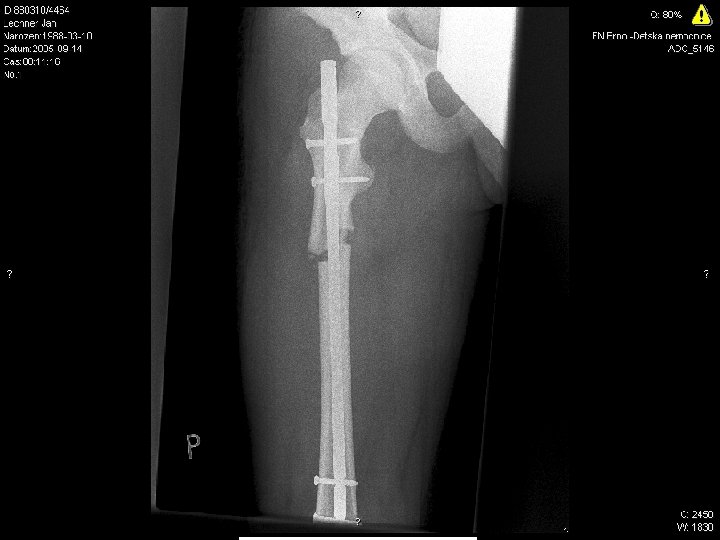

1

2

3

4

5

6

7

8

9

10 17. 4. 2005

Radiodiagnostic test conclusions

10